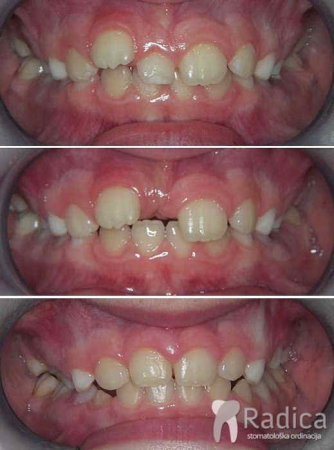

Duboki zagriz, hypodontia (nedostatak) gornjeg desnog lateralnog sjekutića i impakcija gornjeg lijevog očnjaka u nepcu: